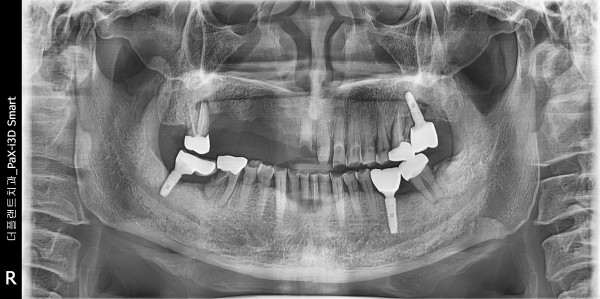

상악 우측 다수 치아의 missing 상태로 환자분이 오셨습니다. 상악 측방 골흡수로 임플란트 식립 동시에 골이식 계획하였습니다.

4개월정도 후에 보철물 장착을 진행하였습니다